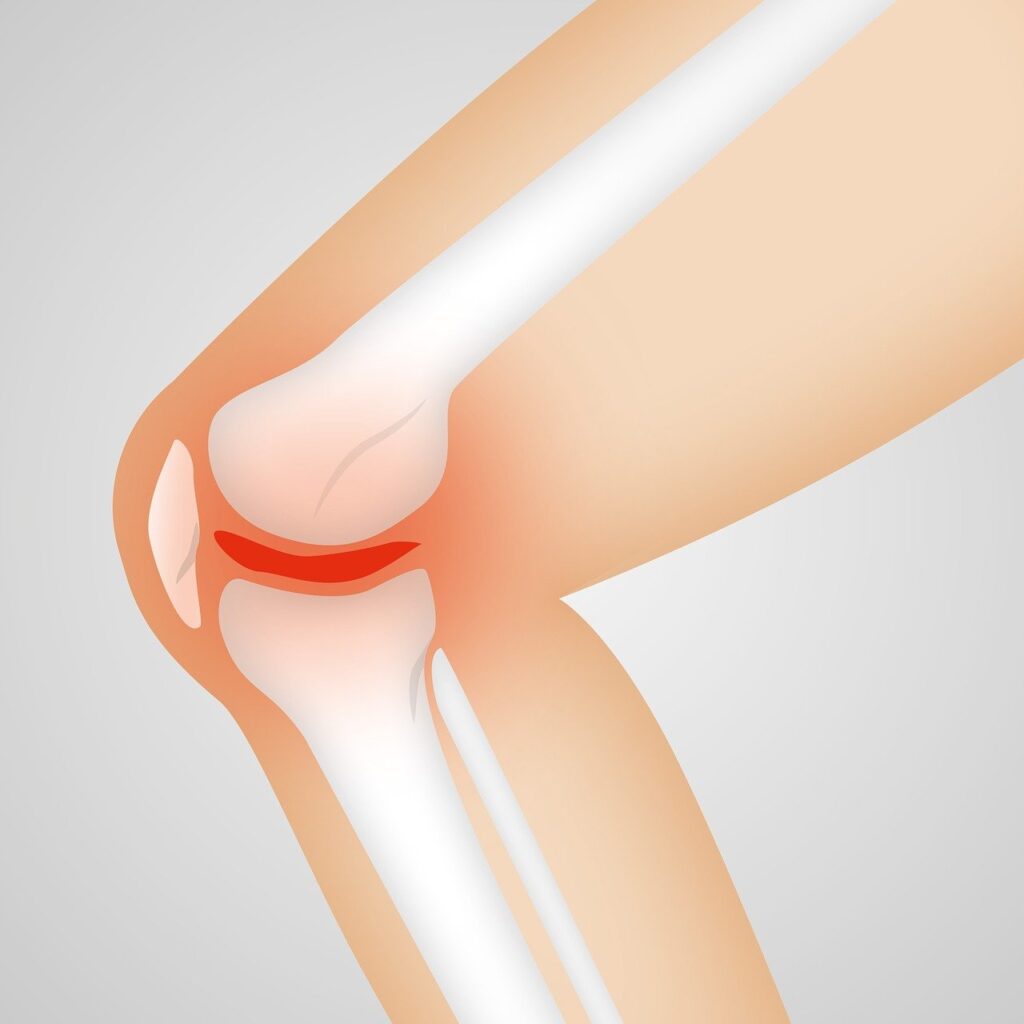

Understanding Synovial Inflammation in Osteoarthritis

When you live with knee osteoarthritis, you become intimately familiar with its symptoms: the deep ache, the morning stiffness, the frustrating loss of mobility. For years, the explanation for this pain has been simple and mechanical: your cartilage is wearing thin, causing bone to grind on bone. While this is true, it is an incomplete […]

How Inflammation Leads to Chronic Knee Pain

For decades, the prevailing narrative surrounding chronic knee pain—specifically knee osteoarthritis—has been mechanical. We have been conditioned to believe that pain is simply the result of “wear and tear.” We visualize our joints like the tires on a car: after miles of use, the tread (cartilage) wears down, leading to a “bone-on-bone” situation that inevitably […]